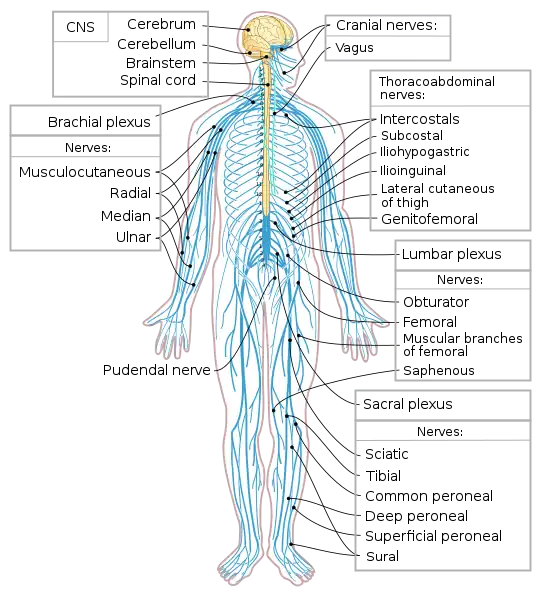

In most animals the nervous system consists of two parts, central and peripheral. The central nervous system contains the brain and spinal cord. The neurons of the central nervous system are interconnected in complex arrangements and transmit electrochemical signals from one to another. The peripheral nervous system consists of sensory neurons, clusters of neurons called ganglia, and nerves connecting them to each other and to the central nervous system. Sensory neurons are activated by inputs impinging on them from outside or inside the body, and send signals that inform the central nervous system of ongoing events. Motor neurons, situated either in the central nervous system or in peripheral ganglia, connect neurons to muscles or other effector organs. The interaction of the different neurons form neural circuits that regulate an organism's perception of the world and its body and behavior.

The Peripheral Nervous System

This system consists of a sensory system that carries information from the senses to the central nervous and then back to the body. Vertebrate PNS structurally consist of left and right pairs of cranial and spinal nerves and associated ganglia. The cranial nerves start from the brain and end mostly in organs of the head and upper body. The spinal nerves start in the spinal cord and spreads into parts of the body below the head. It also consists of a motor system that branches out from the central nervous system, so it targets certain muscles or organs. The motor system can be divided into the somatic system and the autonomic system.